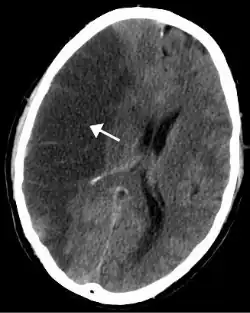

A isquemia em uma parte do cérebro leva ao acidente vascular cerebral (AVC), conhecido como "trombose" (embora nem sempre seja causada por trombos, pode ser também por estenose (estreitamento e/ou bloqueio de uma artéria). Nos membros pode causar gangrena e necessitar amputação. No pulmão pode levar a embolia pulmonar. No intestino é chamada de isquemia mesentérica e pode causar inflamação grave (colite isquêmica). Na pele resulta em descoloração, deixando a pele roxa ou azulada.

- Acidente vascular cerebral ou em outro local;